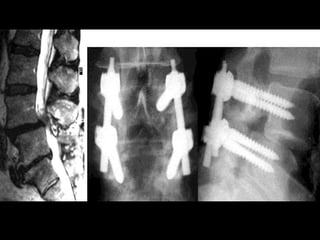

SPINAL FUSION

INDICATIONS:

• Young patients with signs of spondylolisthesis

• Post laminectomy who show instability

• Advanced intervertebral arthritis

• Need to return back to heavy manual work.

TREATMENT